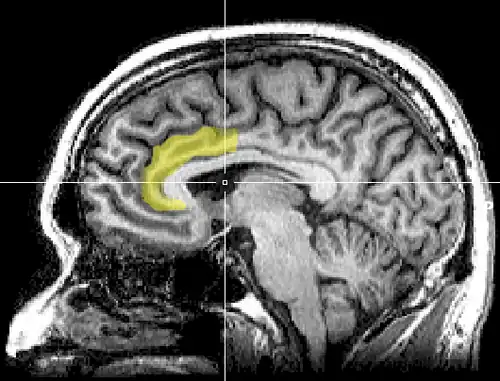

Anterior cingulate cortex

![]() Medial surface of left cerebral hemisphere, with anterior cingulate highlighted | |

In human brains, the anterior cingulate cortex (ACC) is the frontal part of the cingulate cortex that resembles a "collar" surrounding the frontal part of the corpus callosum. It consists of Brodmann areas 24, 32, and 33.